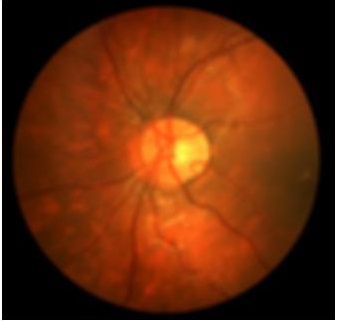

4.2 Retinal Blood Vessel Segmentation Results

We present retinal vessel segmentation results on the DRIVE [16], STARE [6] and CHASEDB1 [5] datasets with , and images respectively. Original images and manual annotations () are downsampled by to get and sets of from methods trained on [2]. and the sets of were used to train different state-of-the art U-Nets for vasculature segmentation [1]. The average accuracy () and sensitivity () for is summarized in Table 2. Better ISR methods should give higher vessel segmentation accuracy and performance of gives a lower bound on the segmentation error. ’s performance is closest to , and establishes its superiority over all competing methods. Figures 4 (a)-(h) show results of vessel segmentation on an example image. ’s performance is most similar to as is evident from the areas of inaccurate segmentation highlighted by yellow arrows. Most of the methods do not segment the finer vasculature structures, while SSR and SR-RF are unable to segment some of the major arteries.

| (a) | (b) | (c) | (d) | (e) | (f) | (g) | (h) |